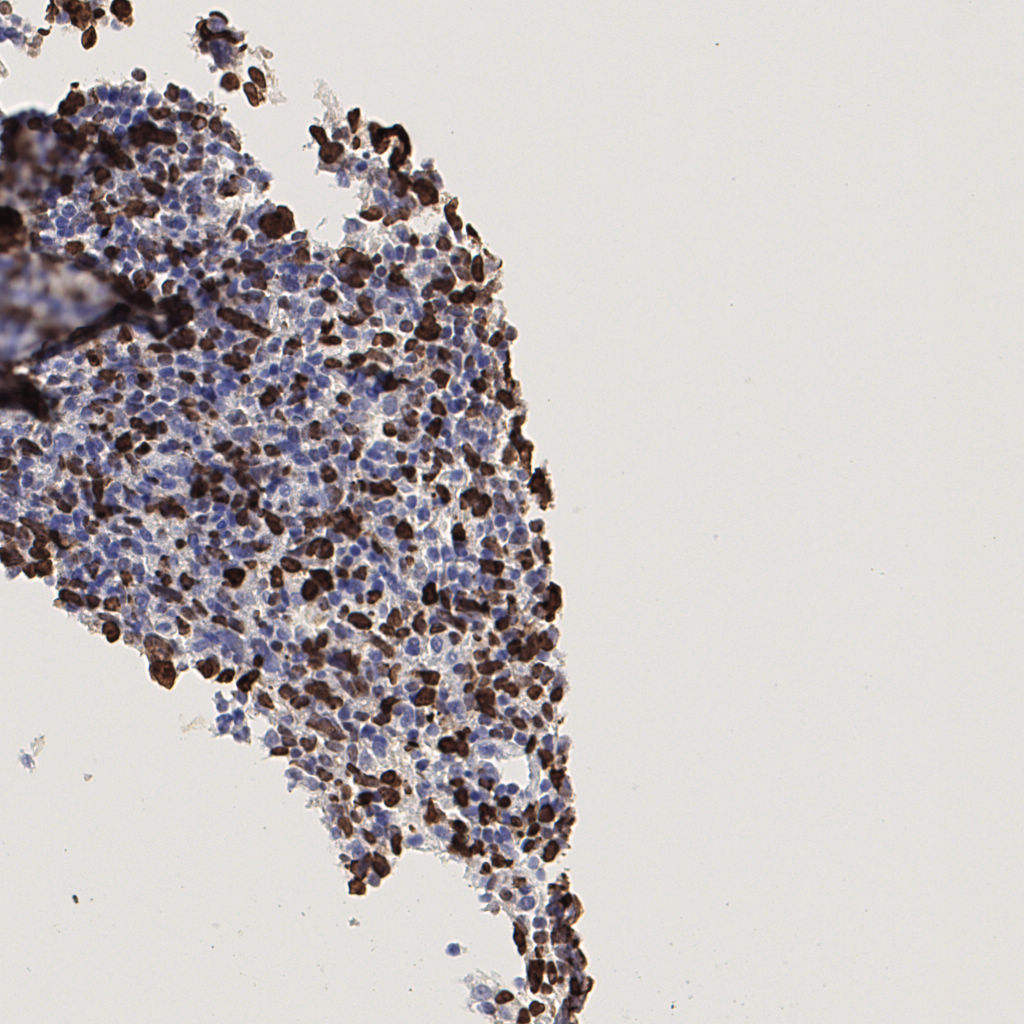

7.85%

Ki67 指数

阴 1104 阳 94

H255858-KI-67.ndpi